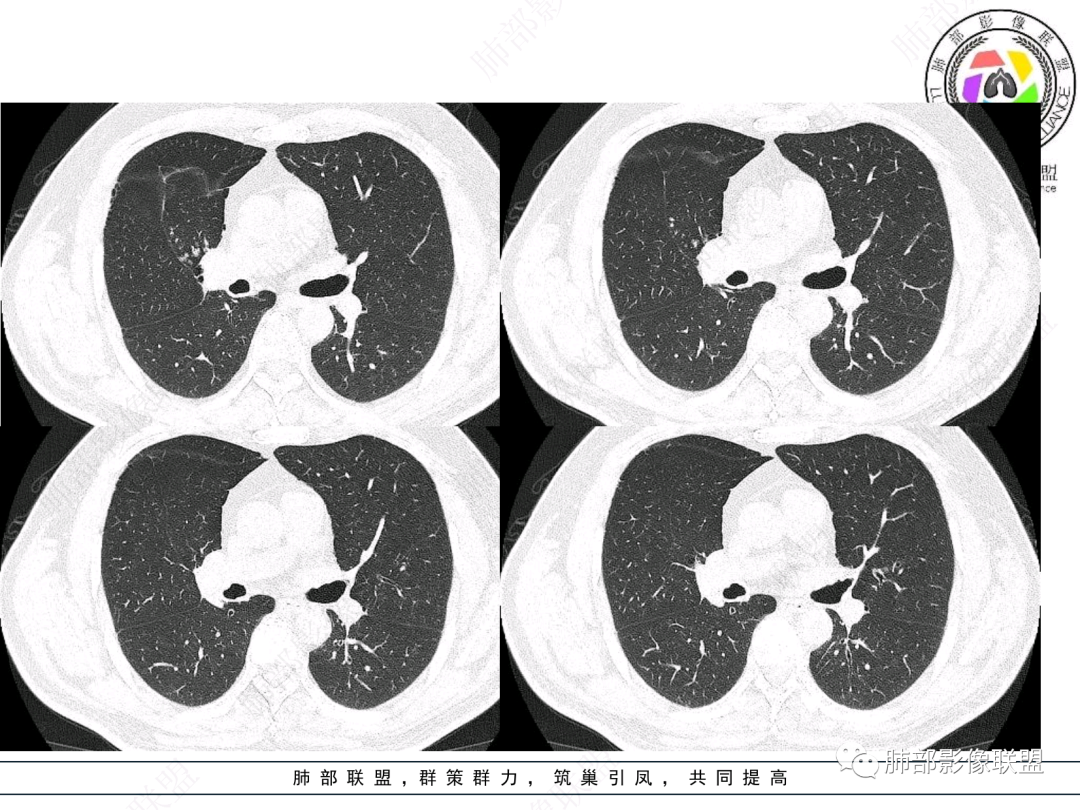

右肺上叶支气管截断,内见软组织密度结节,支气管管壁破坏,病变侵及管外,增强强化明显。右肺上叶沿气管血管束多发斑片影,考虑恶性性病变并阻塞性炎症,鳞癌,神经内分泌肿瘤。

右肺门病灶,支气管腔内堵塞,见有多处低密度影,支气管镜下凹凸不平,直观下不像鳞癌,恶性肯定的,考虑腺样囊性癌可能。

右肺主支气管-上叶支气管腔内结节伴钙化,轻度强化,考虑类癌,鉴别错构瘤与结核。

老年男性,咳嗽咳痰,右肺门增大,右主支气管开口见高密度影,密度不均匀,轻度强化,右肺上叶见多发腺泡结节,支气管管壁增厚,近端粘液栓,支气管镜检查见新生物,考虑鳞癌,鉴别结核。

右主支气管及肺门不规则软组织结节,点状钙化,不均匀强化,气管壁破坏,上叶支气管阻塞,分支粘液栓,血管束增粗,沿支气管分布多发结节,考虑鳞癌合并阻塞性炎症,鉴别结核。

右气管腔内结节,右肺门肿物,有钙化,右侧肺内多发气腔结节,散在,左肺部分支气管壁增厚,首先分析气管内结节,多考虑1鳞癌,形态规则,边缘光滑,宽基底,不太支持,远端阻塞性炎症不典型,2类癌,冰山一角和冰山分离了,不太支持3结核,多为支气管壁广泛增厚钙化,形成结节少,但是肺门肿块有钙化,可作为结核支持点,4黏痰,不像。其他不太懂了,肺内多发磨玻璃结节,并可见支气管手指状扩张,综合分析影像,考虑感染性病变,结核?有没有这样子的气管曲霉呢?向老师们学习。

老年男性,右肺门主支气管腔内软组织肿块影,密度不均,有钙化,右上叶支气管腔部分阻塞,强化较明显,右肺上叶远端散在斑片状高密度影,相应支气管壁厚,树丫状腺泡结节,常规首先考虑结核,鉴别类癌。

右主支气管占位,累及全层,中度强化,远端管壁增厚,似乎花花草草,恶或者低度恶性。疾病谱:鳞(必须首先考虑 概率),腺样囊腺癌(位置 年龄符合 似乎强化也符合),类癌(强化不太支持),良性,结核(妖)。综合考虑腺样囊腺癌。

男性,52岁,右侧主支气管腔内外占位伴点状钙化,病灶大部分位于腔外,右肺上叶散在结节影,气管腔内病灶,动脉期中度强化,静脉期强化减低,首先考虑气管腔内类癌可能,鉴别鳞癌,肺内病变倾向感染性病变;再有气管结核伴肺内播散。

男,52。间断咳嗽、咳痰2周,加重3天。胸部CT:右主、右上叶支气管多发软组织影,跳跃不连续,内可见小环状高密度,点状钙化,管壁破坏,上叶支气管堵塞,远端分支粘液栓,可见小支气管管壁增厚、管腔狭窄,沿支气管分布多发结节,无大片炎症不张。考虑:TB?NTM?鉴别Ca并阻塞性炎症。

肺门肿块,支气管铸型,远侧小花小草,考虑鳞癌,右主支气管结节,鳞癌?二元论:腺样囊性癌?

中年男性,咳嗽咳痰,右肺上叶近肺门肿块,上叶支气管近端阻塞,内有粘液栓,右肺上叶多发结节影有小空泡,沿支气管血管束分布,血象不高,CRP及PCT不高,XPERT阴性,结核可能性不大,考虑恶性肿瘤可能,类癌?腺样囊性癌?鳞癌?远端肺内的考虑阻塞性炎症还是转移?

患者中老年男性,咳嗽咳痰2周,无发热、咯血,伴胸闷、乏力及盗汗等,右上叶沿支气管血管束分布结节样变,管壁增厚;右肺门肿块,形态不规则、密度欠均匀,似有钙化,轻强化,主气道下端及右主支气管开口处见新生物,强化不支持类癌,镜下病变形态不大支持腺样囊性癌,考虑鳞癌可能性大,右肺上叶病变结核可能。

右肺上叶支气管开口见阻塞物影及强化,息肉样向腔内外浸润性生长,并有颗粒钙化,右肺上叶段支气管主干增粗及密度增高,见指套征,支气管血管旁见多发小斑点,小斑片影阻塞性炎性病灶〈小花小草表现〉,支气管镜示新生物血供丰富(结核完全排除),方向恶性,符合鳞癌特点,与小细胞Ca鉴定,临床专科支气管镜取材活检明确诊断。

腔内肿物,强化不均匀,强化程度为轻中度强化(CT值增加25HU),且强化特点为快进快出,右肺上叶支气管责任区域的阻塞性炎症加痰栓(气管镜也证实右上叶支气管内痰多)。这些均明确指向鳞癌。

屈运良:

毛勤香:

这个病例比较好,我们的观察点在哪?这是右上叶支气管病变,需要了解:腔内、壁、腔外、远端,腔内有软组织密度影,近端膨隆。

影像上分析的观察点:腔内、壁、腔外、远端,然后就是远端肺组织、淋巴结、肺血管、胸膜、其他肺部,这个人就是阻塞性炎症为主。